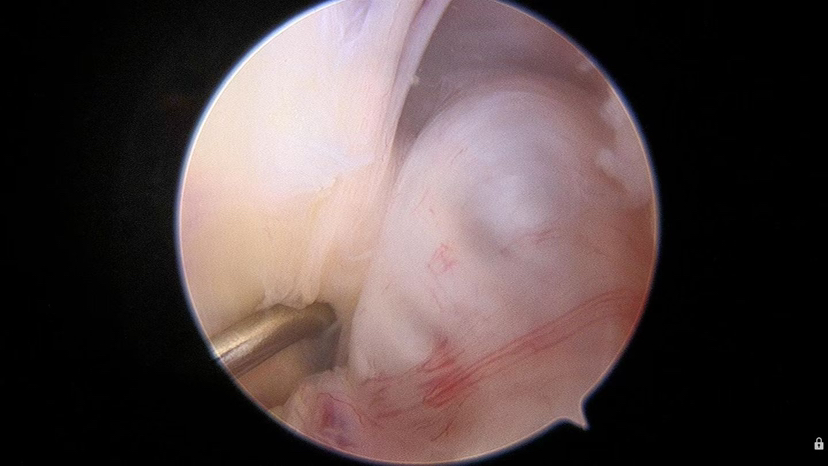

【关节镜手术切除】:无论是否有症状,关节镜手术切除均为主要的治疗方法,创伤小,恢复快!一般认为在不损害交叉韧带功能的前提下,应完整切除囊壁并防止囊液播散,从而达到防止复发的目的。

示例: